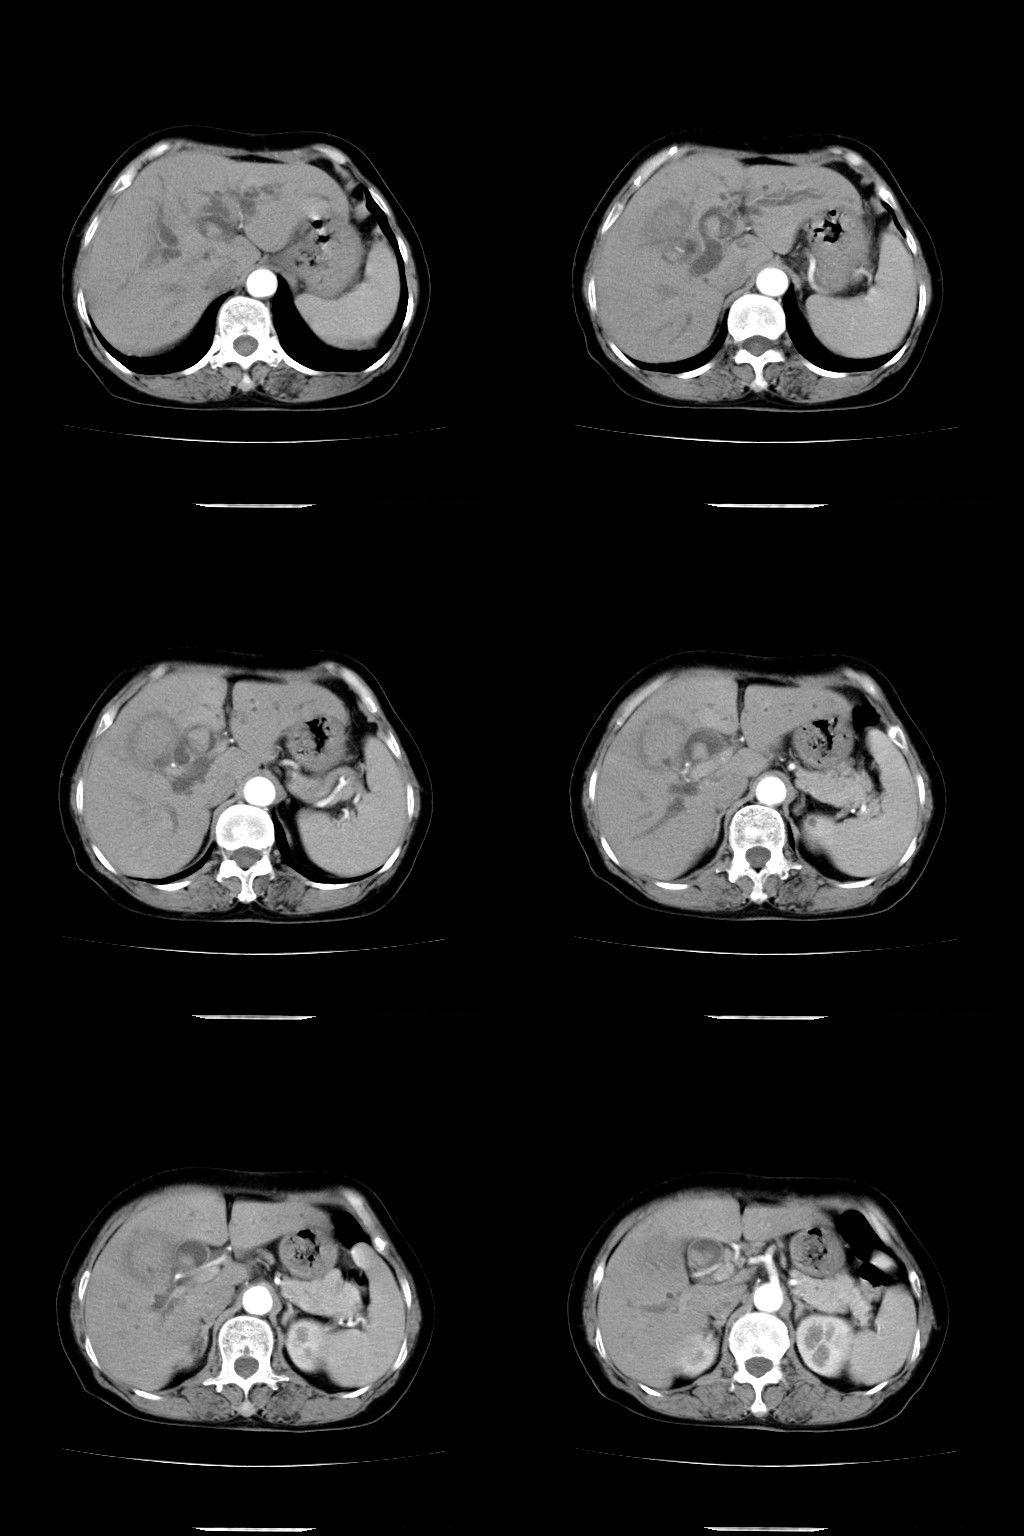

以下是引用随光逐影在2009-1-22 9:27:00的发言:[br]1)考虑胆囊癌侵犯肝脏。2)肝总管及胆总管多发性结石并肝内、外胆管扩张。

以下是引用余辉在2009-1-22 8:49:00的发言:[br]平扫肝内胆管扩张,右肝前叶球形低密度影,边缘较清楚,胆囊壁增厚,内可见较大高密度影,胆总管内亦可见高密度影,胰头区结构欠清。[br]增强动脉期见右肝前叶球形变灶明显增强,边缘见环状低密度区。胆囊见高密度影无增强,胆总管明显扩张,内见块状高密度影,周围环以低密度区,边界清楚。[br]静脉期见右肝前叶病灶持续增强,密度较动脉期增高。[br]考虑1胆囊及胆总管结石伴梗阻性胆系扩张,胆囊胆管炎。[br] 2右肝前叶占位性病变,强化规律符合胆管细胞癌,建议结合其他检查协诊